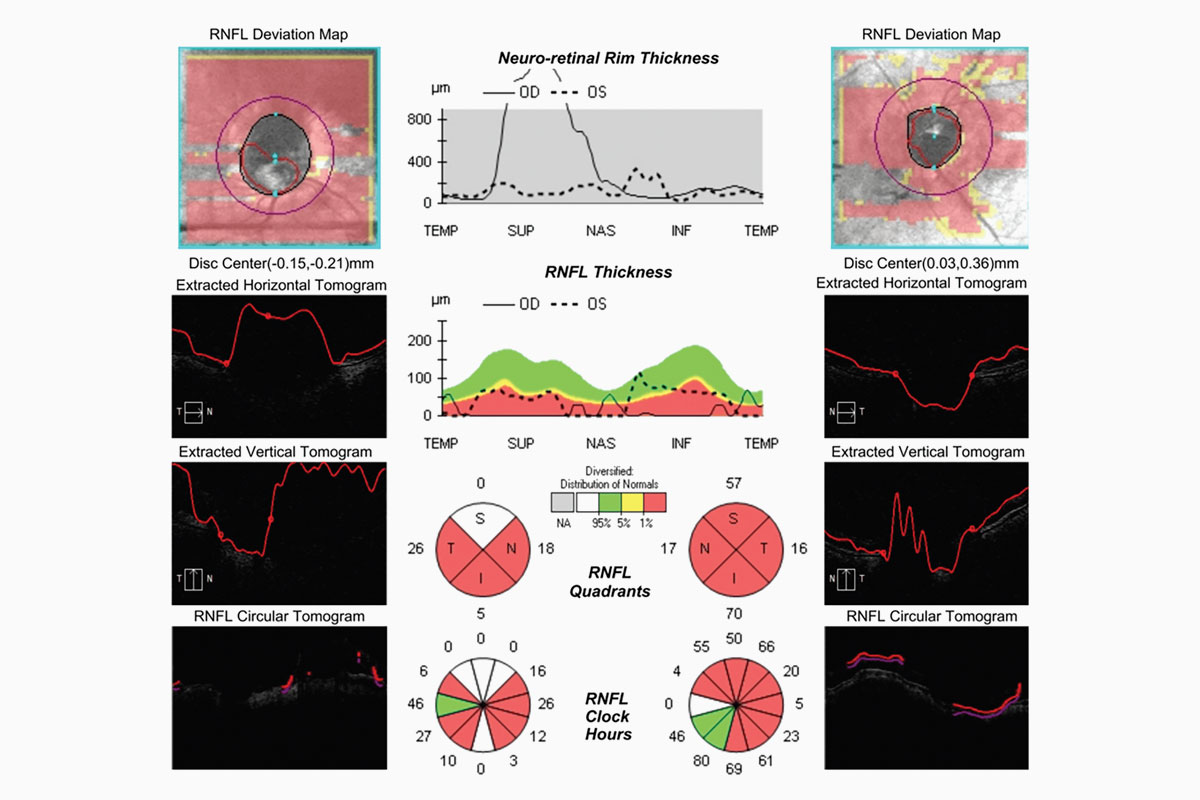

- Hombre de 72 años con glaucoma de ángulo abierto y síndrome de dispersión pigmentaria y amplitud de ángulo variable.